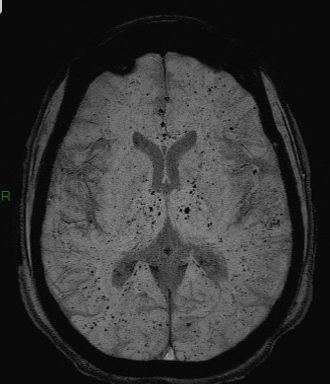

Microhemorragias hipertensivas

cerebelo, tálamo, ponte, núcleos da base

Múltiplas lesões, sendo o local mais frequente a junção da substância branca e cinzenta (75%), corpo caloso, parte superior do tronco, núcleos da base e cápsula interna;

Lesões da LAD podem ser hemorrágicas ou não. As lesões hemorrágicas se apresentam frequentemente como Lesões hiperdensas ovaladas pequenas (TC) e Multiplos pontinhos negros (T2 *). Quando não hemorrágicas podem cursar com hipersinal FLAIR.